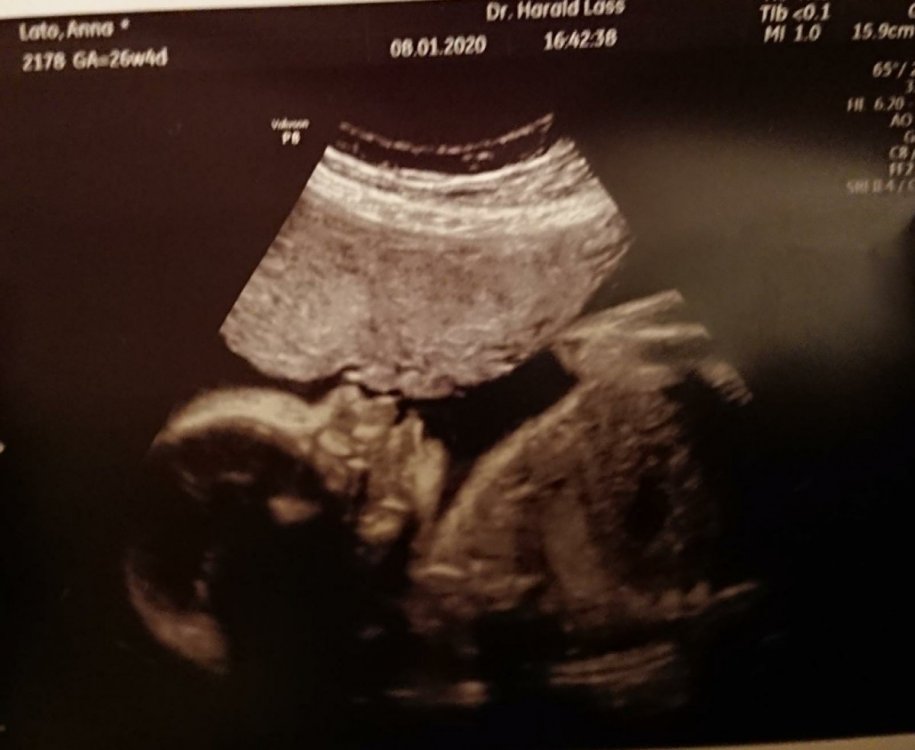

2. Juz wszystko w porzadku 🙂 widze wszystkie posty i moge sie zalogowac. Jestem wlasnie po wizycie. Wszystko jest w porzadku. Mala wazy 1005g 🙂 Szyjka dluga na 4,4cm i zamknieta. Wody plodowe, przeplywy bardzo dobre. Jutro ide na glukoze, na nastepna wizyte (30.1) mam przyjsc z zastrzykiem immunoglobulina Rh. No i szczepienie przeciw krztuscowi chce jeszcze zalatwic pod koniec stycznia. W przyszlym tygodniu mam termin w szpitalu z polozna. Black Panther, u mnie po operacji tarczycy troche trwalo, zeby ustawic prawidlowo dawke. Raz bylo za malo, raz za duzo. Ale po jednej tabletce to raczej nie jest mozliwe. Magdaa, gratuluje coreczki kolezanke, chociaz porod faktycznie ciezki... Mama88, oj nie zawsze mam sily, a czasem plecy daja mi mocno popalic, ale nie zastanawiam sie specjalnie tylko jakos sie zwlekam 😉